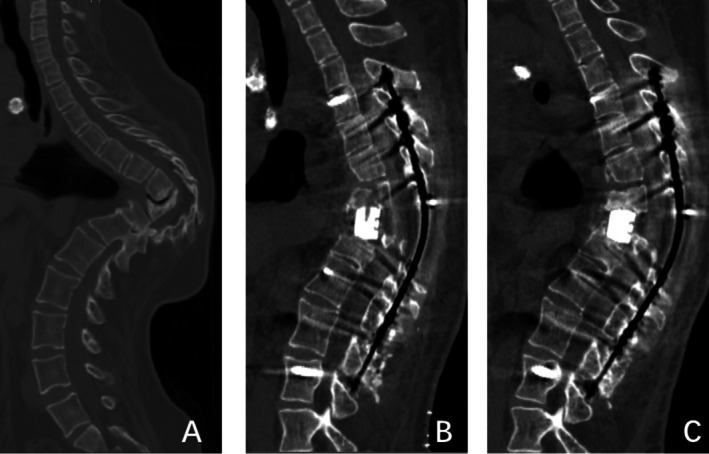

目的:大量研究报道了颈腰椎退行性疾病患者椎间融合器(IFDs)匹配不良的表现及影响因素。然而,目前还没有研究解决在后路脊柱切除术(PVCR)手术中使用ifd匹配的问题。本回顾性影像学研究的目的是分析PVCR后ifd匹配不良的相关危险因素。方法:回顾了2006年6月至2024年7月期间92例PVCR后使用ifd的患者的数据。将ifd植入失败、相邻椎体骨折、沉降大于5mm、角度形成超过10°、错位(定义为超过匹配界面外缘的ifd的三分之一)作为筛选指标,将患者分为匹配不良组和匹配组。通过单因素和多因素logistic回归分析评估匹配不良的潜在危险因素。以受试者工作特征曲线下面积(AUC)评价多元回归模型。结果:92例患者中37例(40.2%)匹配不良。单因素logistic回归分析显示,术前、术后矢状Cobb角、截骨面夹角、置入椎体总数、切除椎体数、ifd高度、钛网或人工椎体的使用是导致匹配不良的潜在危险因素。多因素逐步回归分析显示,术前矢状Cobb角(OR = 1.053, p = 0.001)、截骨面夹角(OR = 1.152, p = 0.003)、ifd高度(OR = 1.058, p = 0.033)是吻合不良的独立危险因素。对于匹配差的情况,该多元回归模型的总体预测性能(AUC = 0.872)令人满意。结论:在PVCR中使用ifd与高的即时匹配不良率相关。术前矢状Cobb角、截骨面夹角、ifd高度是吻合不良的独立危险因素。

Methods: Data from 92 patients using IFDs following PVCR between June 2006 and July 2024 were reviewed. IFDs implantation failure, adjacent vertebral fractures, subsidence greater than 5 mm, angle formation exceeding 10°, and malposition (defined as one-third of the IFDs exceeding the outer edge of the matching interface) were used as screening indicators to divide patients into poor matching and matching groups. Potential risk factors of poor matching were assessed through univariate and multivariate logistic regression analysis. The multiple regression model was evaluated by the area under the receiver operating characteristic curve (AUC).

Results: Among the 92 patients, 37 (40.2%) experienced poor matching. Univariate logistic regression analysis revealed that the preoperative and postoperative sagittal Cobb angles, the angle between osteotomy surfaces, total instrumented vertebrae, the number of vertebrae resected, the height of IFDs, and the use of titanium mesh or artificial vertebral bodies were potential risk factors for poor matching. Backward stepwise multivariate logistic regression analysis indicated that the preoperative sagittal Cobb angle (OR = 1.053, p = 0.001), the angle between osteotomy surfaces (OR = 1.152, p = 0.003), and the height of IFDs (OR = 1.058, p = 0.033) were independent risk factors for poor matching. The overall predictive performance of this multiple regression model (AUC = 0.872) for poor matching was deemed satisfactory.